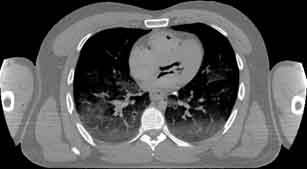

Visible Human male: Sectio transversalis 1440

CT